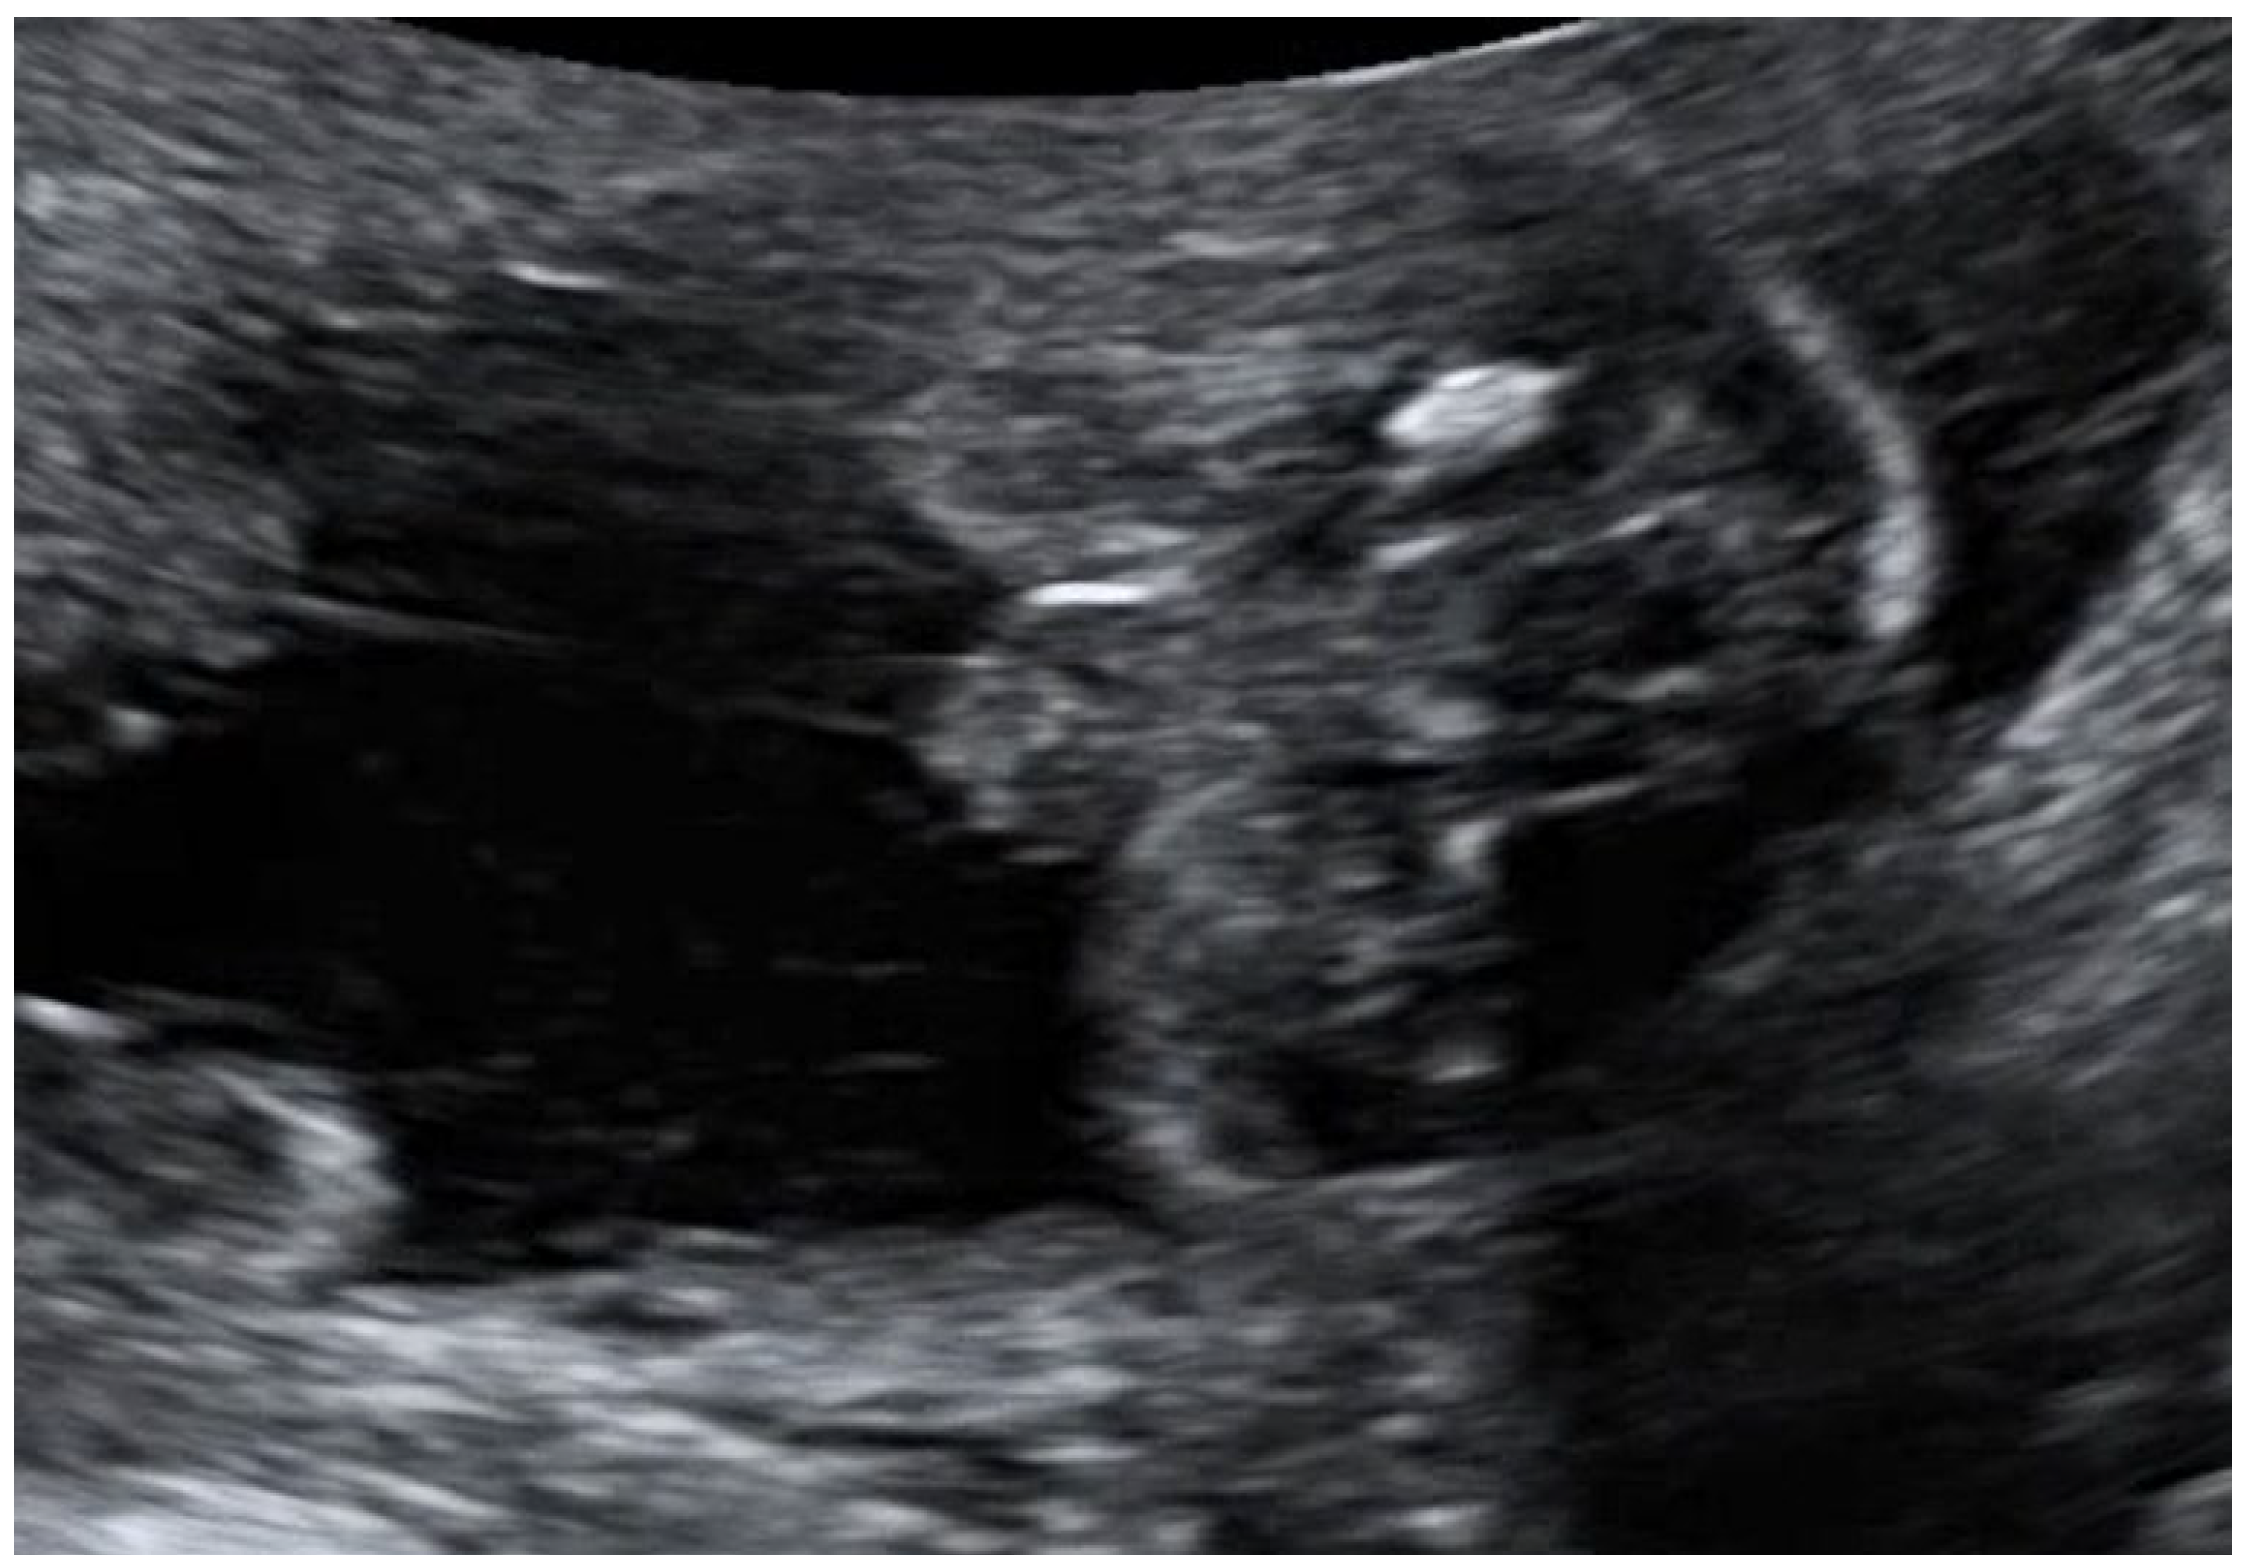

- To present prenatal features in a case of MIRAGE syndrome diagnosed prenatally in a fetus with severe growth restriction, ambiguous genitalia, hyperechogenic bowel, and oligohydramnios at the mid-gestation routine anomaly scan, at 22 weeks of pregnancy.

3.1. Case Presentation